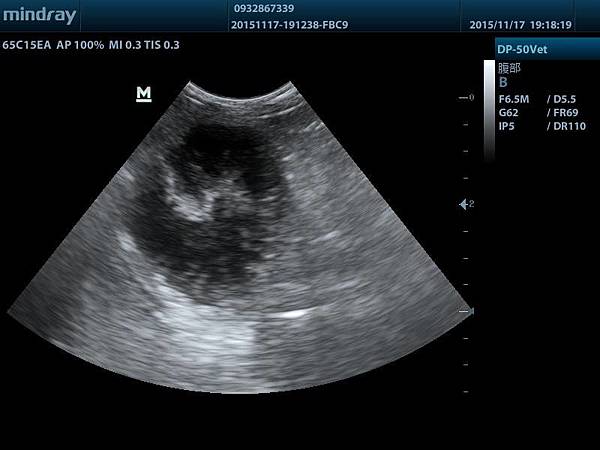

安咕來檢查的時候發現有肝腫瘤+膽囊黏液囊腫

201511171918200005ABD.JPG

可以看到腫瘤非常龐大